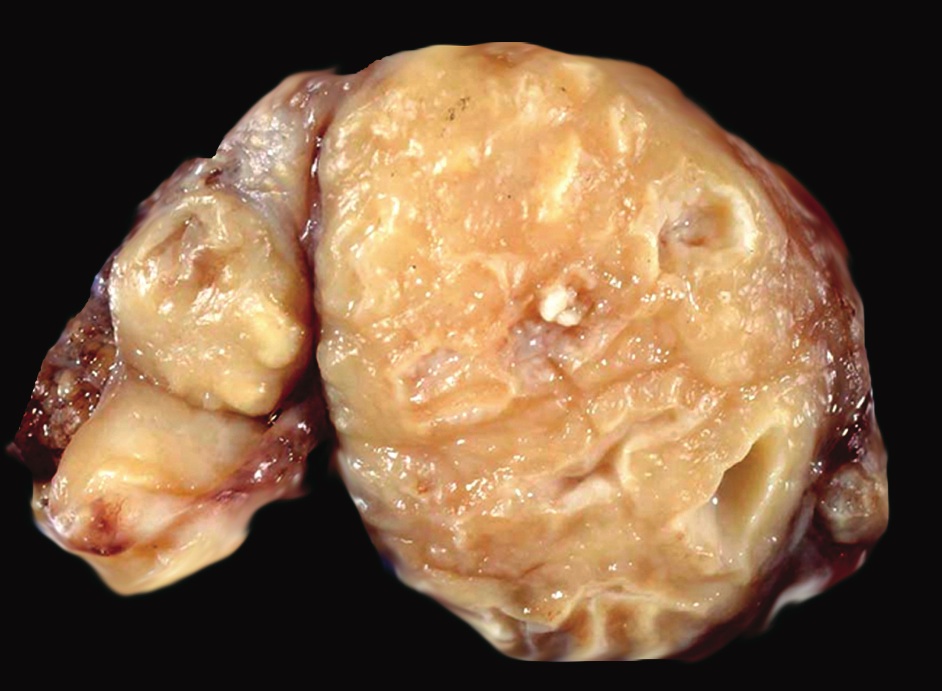

Gross description

Gross images

Contributed by Mark R. Wick, M.D.

Gross description

- Large multinodular mass that resembles carcinoma with multiple foci of caseous necrosis

Gross images

Contributed by Mark R. Wick, M.D.